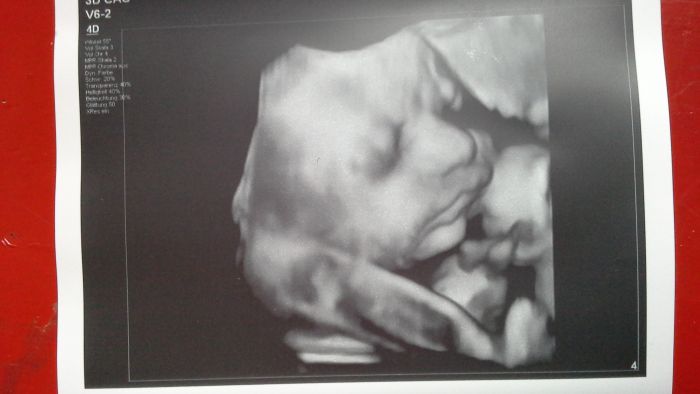

Jeee, ted to pro zmenu klaplo s fotkou, ale misto srandovnich smajliku jsou otazniky. Neva, hlavne ze je tam obrazek spiciho Ruzenaka. Dneska jsme meli kontrolu v10.00 a to je doba, kdy byva v klidu.

Míšo, malej je moc krásnej! To už je opravdu nádherná fotka, jsi tedy o týden dál než já, ono se to miminko týden od týdne zakulacuje a tady už je fakt suprově vidět:-)...jinak taky mám malou hlavičkou dolů, ale prý se ještě může několikrát otočit. A ještě jednou gratuluju!

[1048489] Miso, to je opravdu krasna fotka! To nase mimi na 3D takhle opravdu nevypadalo. Vsechno mame hur prehledne kvuli te placente. Ja jdu na uzv v 31+6, tak porovname :-)

[1048587] Dobre rano holky!  Je fakt, ze jak prcek pribira, tak se ty faldiky rovnaji a je lip videt. Ma uz skrane jak krecek. Ale nejvic jsme se s doktorkou zasmaly tomu nosiku. Ja mam spis trochu prsak, kdezto muj uplne stejny jak prdola na fotce. Doktorka mrkla na pritele a hned rekla, ze se vetsinou z tehle fotek jeste neda zadna podoba urcit, ale ten sosak, ze je jeho. Prisaham, ze se cervenal a porostl. Myslim ten velky!Wink Ja to mam s pohyby podobne s Tuli. Ty silnejsi citim skoro az pod zebry a ty slabsi dole nebo na levem boku. To budou asi rucicky.